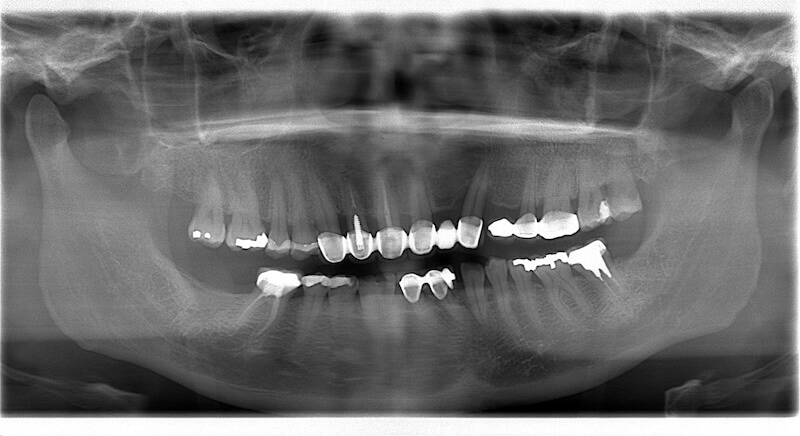

牙齦腫大出血也是高血壓藥物的副作用之一,專業牙周專科醫師會將藥物副作用考量在內制定完善牙周治療計劃。本案例分享葉立維醫師如何協助高血壓患者 Ms. H 解決他院無法改善的牙齦腫大問題,並透過完整牙周病療程與DSD數位微笑設計,讓 Ms.H 恢復自信笑容。